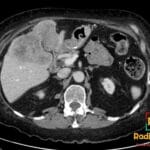

- Radiology Cases: Images with a to-the-point discussion highlighting the specific diagnostic criteria.

- Radiology Case of the Day Collection: Aunt-Minnie Board Cases for Rapid Review.

- Radiology Spotters: 700+ spot / “Aunt-Minnie” cases divided into sets of 10 each!